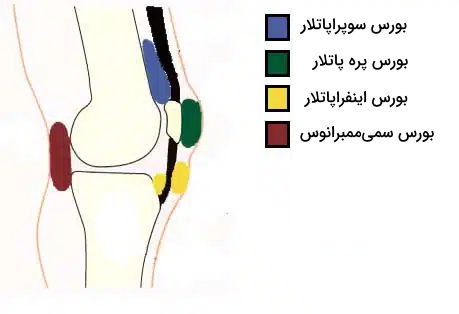

کپسول مفصل چندین ساختار کیسهای ایجاد میکند که مملو از مایع هستند و «بورس» (Bursae) نام دارند. بورسها اصطکاک درونی مفصل زانو را کاهش میدهند. در ادامه با چهار بورس شاخص موجود در آناتومی مفصل زانو بیشتر آشنا میشویم.

- «بورس سوپراپاتلار» (Suprapatellar Bursa): در بالای کشکک بین استخوان ران و تاندون ماهیچه چهارسر ران قرار دارد.

- «بورس پره پاتلار» (Prepatellar Bursa): در جلوی کشکک بین این استخوان و پوست قرار گرفته است.

- «بورس اینفراپاتلار» (Infrapatellar Bursa): زیر کشکک بین رباط کشککی و استخوان درشتنی واقع شده است.

- بورس نیمغشایی یا «بورس سمیممبرانوس» (Semimembranosus Bursa): در پشت مفصل زانو، بین ماهیچه نیمغشایی و سر داخلی ماهیچه دوقلو قرار دارد.